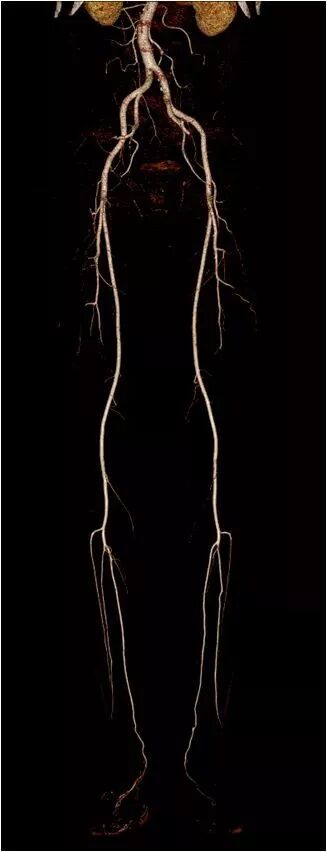

完成全身动脉检查仅需3秒

胸部肺动脉扫描检查,扫描时间不到1秒,可以得到清晰的肺动脉图像,避免肺静脉干扰。

完成2米范围全身动脉扫描仅需3秒,即可得到清晰图像。

全新0兆球管可持续行大范围扫描,轻松应对双下肢动脉CTA检查。